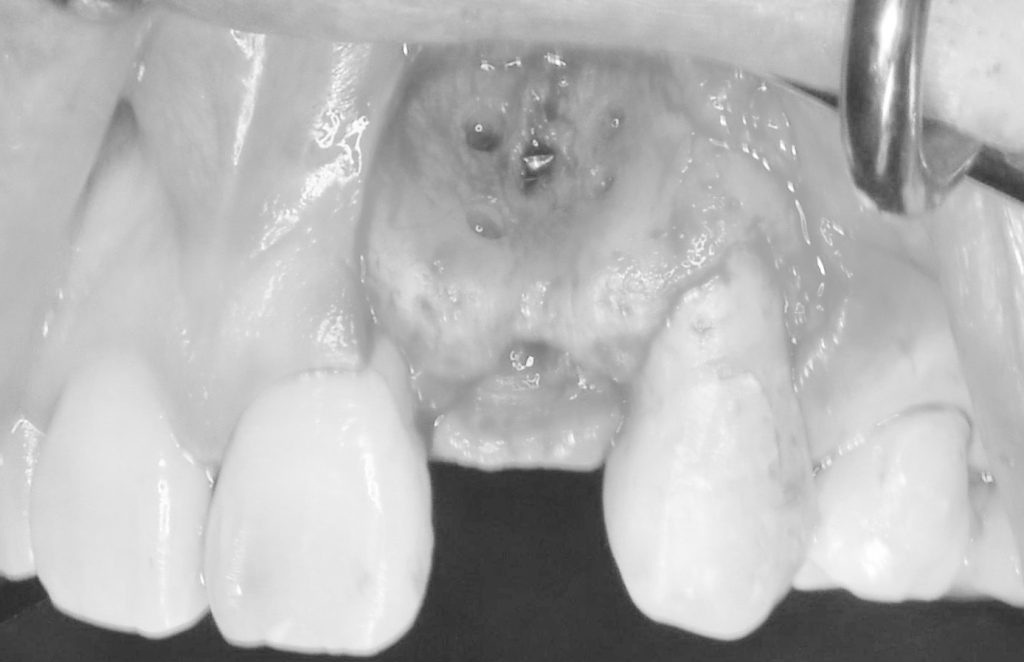

下記の症例は骨幅が狭小でこのままではインプラント治療を行う事ができず、また適切な補綴物を装着できない為、見た目が悪くお手入れしにくい被せ物を装着する事になります。

その為、当医院では様々な骨造成手技を用い、長期的に安定したインプラント周囲骨そして、審美的な結果を左右する結合組織移植を同時に行い、周囲環境を改善していきます。